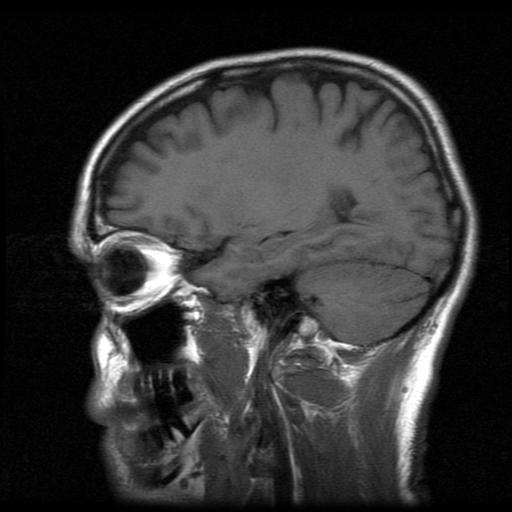

Determining the Cause of Brain Damage

The next step is to determine what caused the brain damage. Was it a physical injury at birth? To find out, your child may need a CT scan, MRI or other physical tests. In some cases, your baby may even need surgery to stop the bleeding in the brain, to relieve pressure or to repair cranial fractures. Medications may help control seizures and other behavioral problems. Children may also benefit from physical and behavioral therapy. The following factors may cause infant brain damage at birth – compression or fractures of the skull, bleeding in the brain, oxygen deprivation or asphyxia and maternal infections.